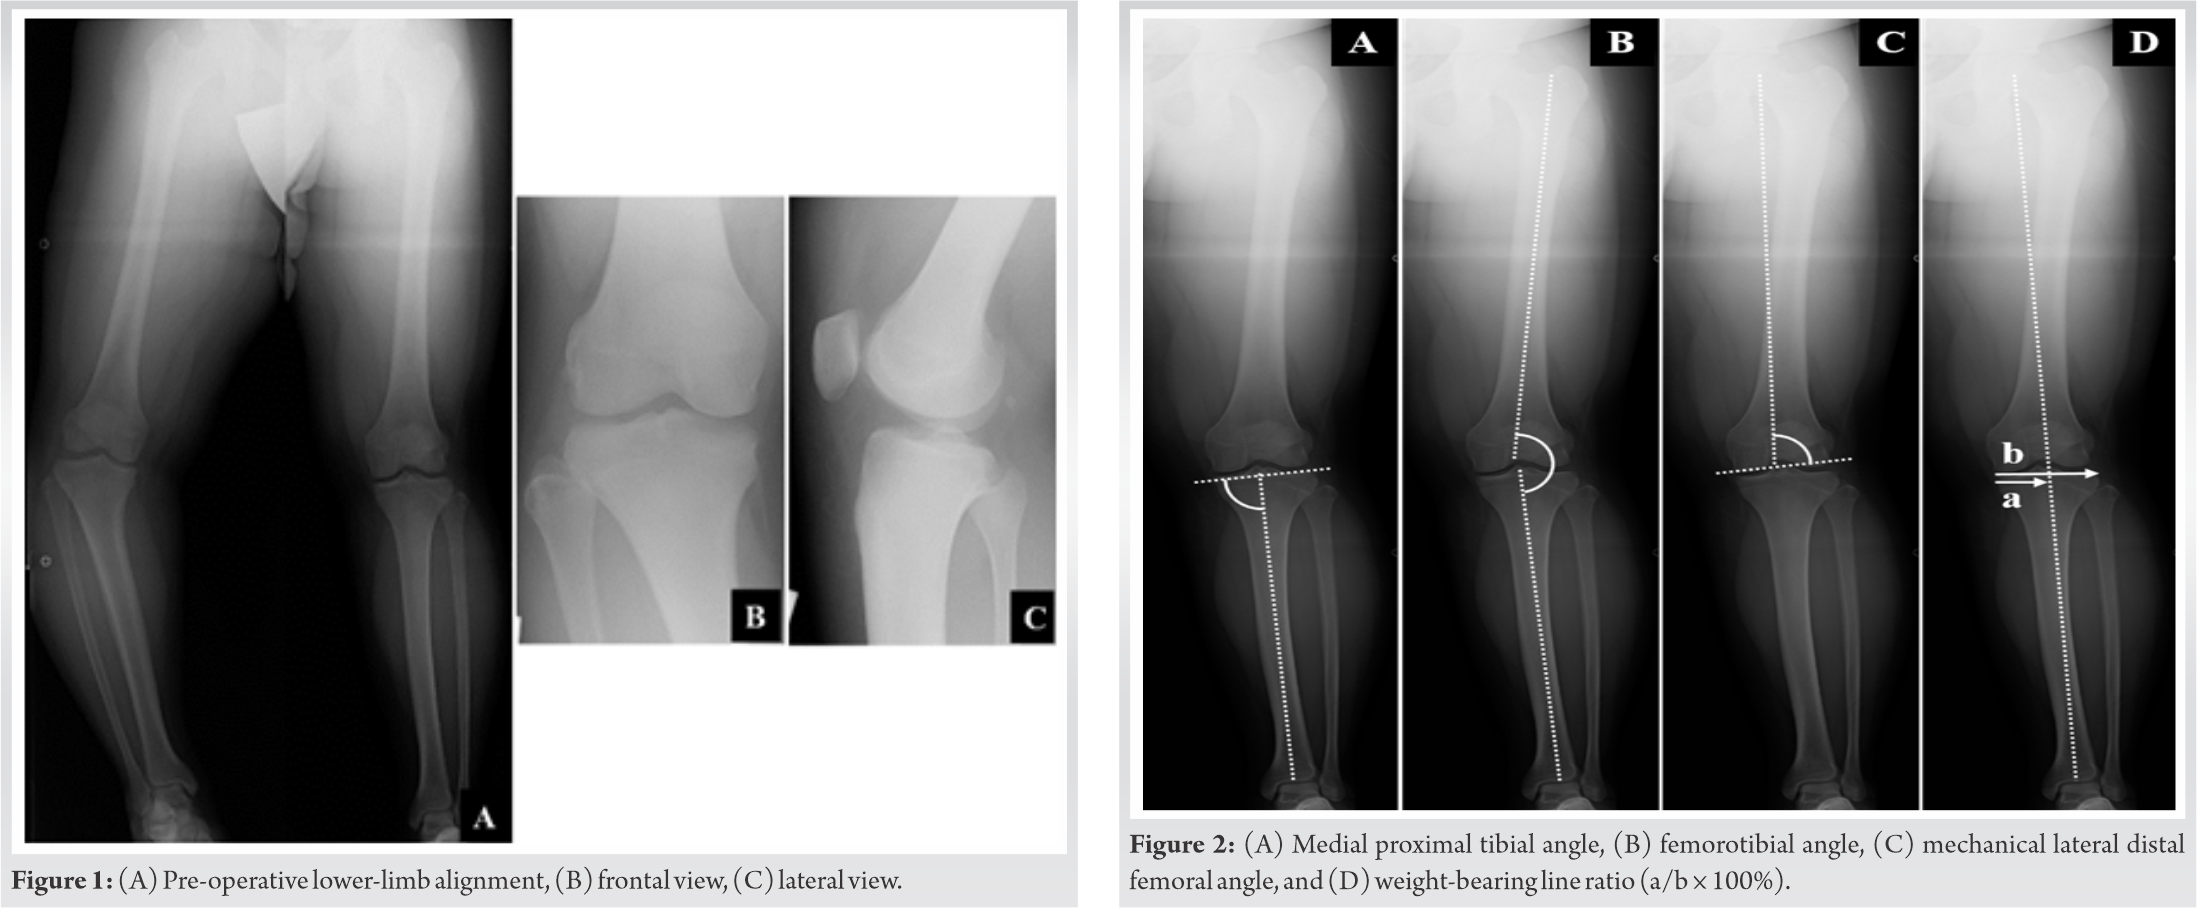

The range of motion (ROM) was 0° in extension and 135° in flexion. The subscales of pre-operative knee injury and osteoarthritis outcome score (KOOS) [7] (symptoms; pain; daily activities; sports and recreational function; and quality of life) were 89.29, 80.56, 82.35, 45, and 75, respectively. Bilateral anteroposterior long-leg weight-bearing radiograph (Fig. 1A-C) showed that the medial proximal tibial angle (MPTA), femorotibial angle (FTA), and the mechanical lateral distal femoral angle (mLDFA) in the right/left legs were 70°/89°, 204°/171°, and 94°/93°, respectively (Fig. 2A-C).The weight-bearing line ratio (WBLR) and non-weight bearing line ratio WBLR (non-WBLR) in the right/left legs were found to be −62%/54%, and −19%/42%, respectively. WBLR is defined as the horizontal distance from the medial edge of the tibial plateau to the WBL divided by the width of the tibial plateau (Fig. 2D). Detailed deformities were examined by using three-dimensional (3D) computed tomography (CT) images (Fig. 3A and B). Magnetic resonance imaging showed no abnormalities in the intra-articular anatomical structures, and the epiphyseal line was almost closed (Fig. 4A-C).